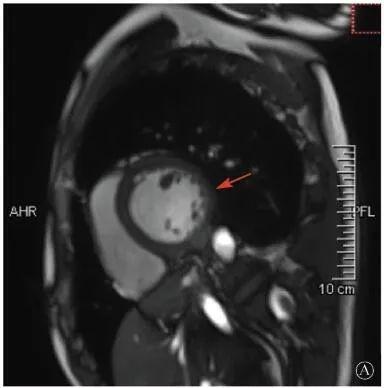

左室壁较广泛心外膜下延迟强化,可见左室下后壁肌小梁增多(箭头所示)

图1 患者外院磁共振心肌灌注延迟动态成像